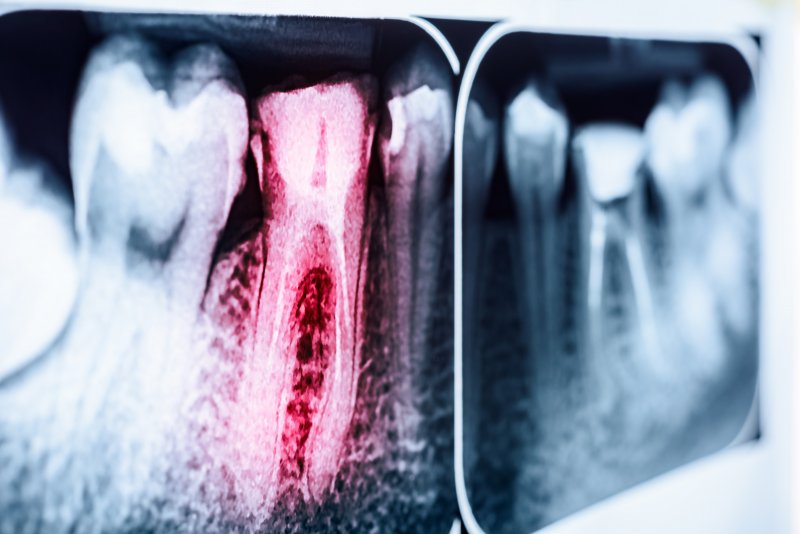

The average root canal has a long-term success rate of 80-95%, but it can still go wrong at times. You might have to redo the procedure for one (or more) of the following reasons:

- Tricky Canal Anatomy – A tooth with narrow, curved, or complex canals may hide bacteria that should be removed. Should that happen, you may suffer a re-infection.